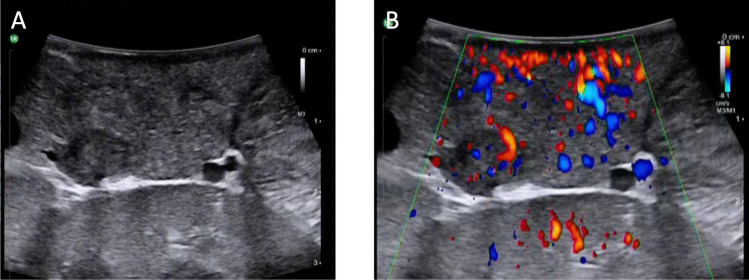

Recent findings: Improvements in surgical techniques allow for more locally advanced and metastasised GEP-NETs to be resected. Laparoscopic and robotically--assisted approaches are increasingly being utilised in the resection of selected GEP-NETs and are facilitated by novel intraoperative tumour localisation tools and parenchyma-sparing methods. At the same time, some authors suggest that indications for formal resections of small well differentiated non-functioning pancreatic NETs and appendiceal NETs should be more restrictive. Advancements in surgery allows for tissue-sparing resections of GEP-NETs. Indications for surgical resection and the extent of the procedure are highly dependent on GEP-NET size, localisation and grading. Robotically assisted surgeries with intraoperative ultrasound and visualisation methods as well as vessel-sparing radical retrograde lymphadenectomies for small intestinal NETs seem to be the future of GEP-NET surgery.